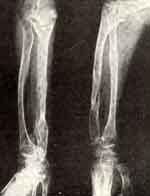

Множественная экзостозная хондродисплазия

Множественная экзостозная хондродисплазия со стреловидной деформацией недоразвитой локтевой кости и вывихом лучевой кости в локтевом суставе у больной 12 лет: до лечения, косая удлиняющая остеотомия локтевой кости с дистракцией аппаратом Илизарова и исправление деформации.

2/VII 1971 г. под наркозом больной произведена операция — остеотомия локтевой кости и наложение аппарата Илизарова с фиксацией дистального фрагмента локтевой кости дистракционнои фиксирующей спицей. В процессе удлинения произошло вправление головки лучевой кости и образование регенерата в области средней трети.

Аппарат был снят, головка удерживалась у головчатого возвышения, движения в локтевом суставе сохранились полностью, в лучезапястном суставе — также. Супинация и пронация ограничены в пределах 15°.